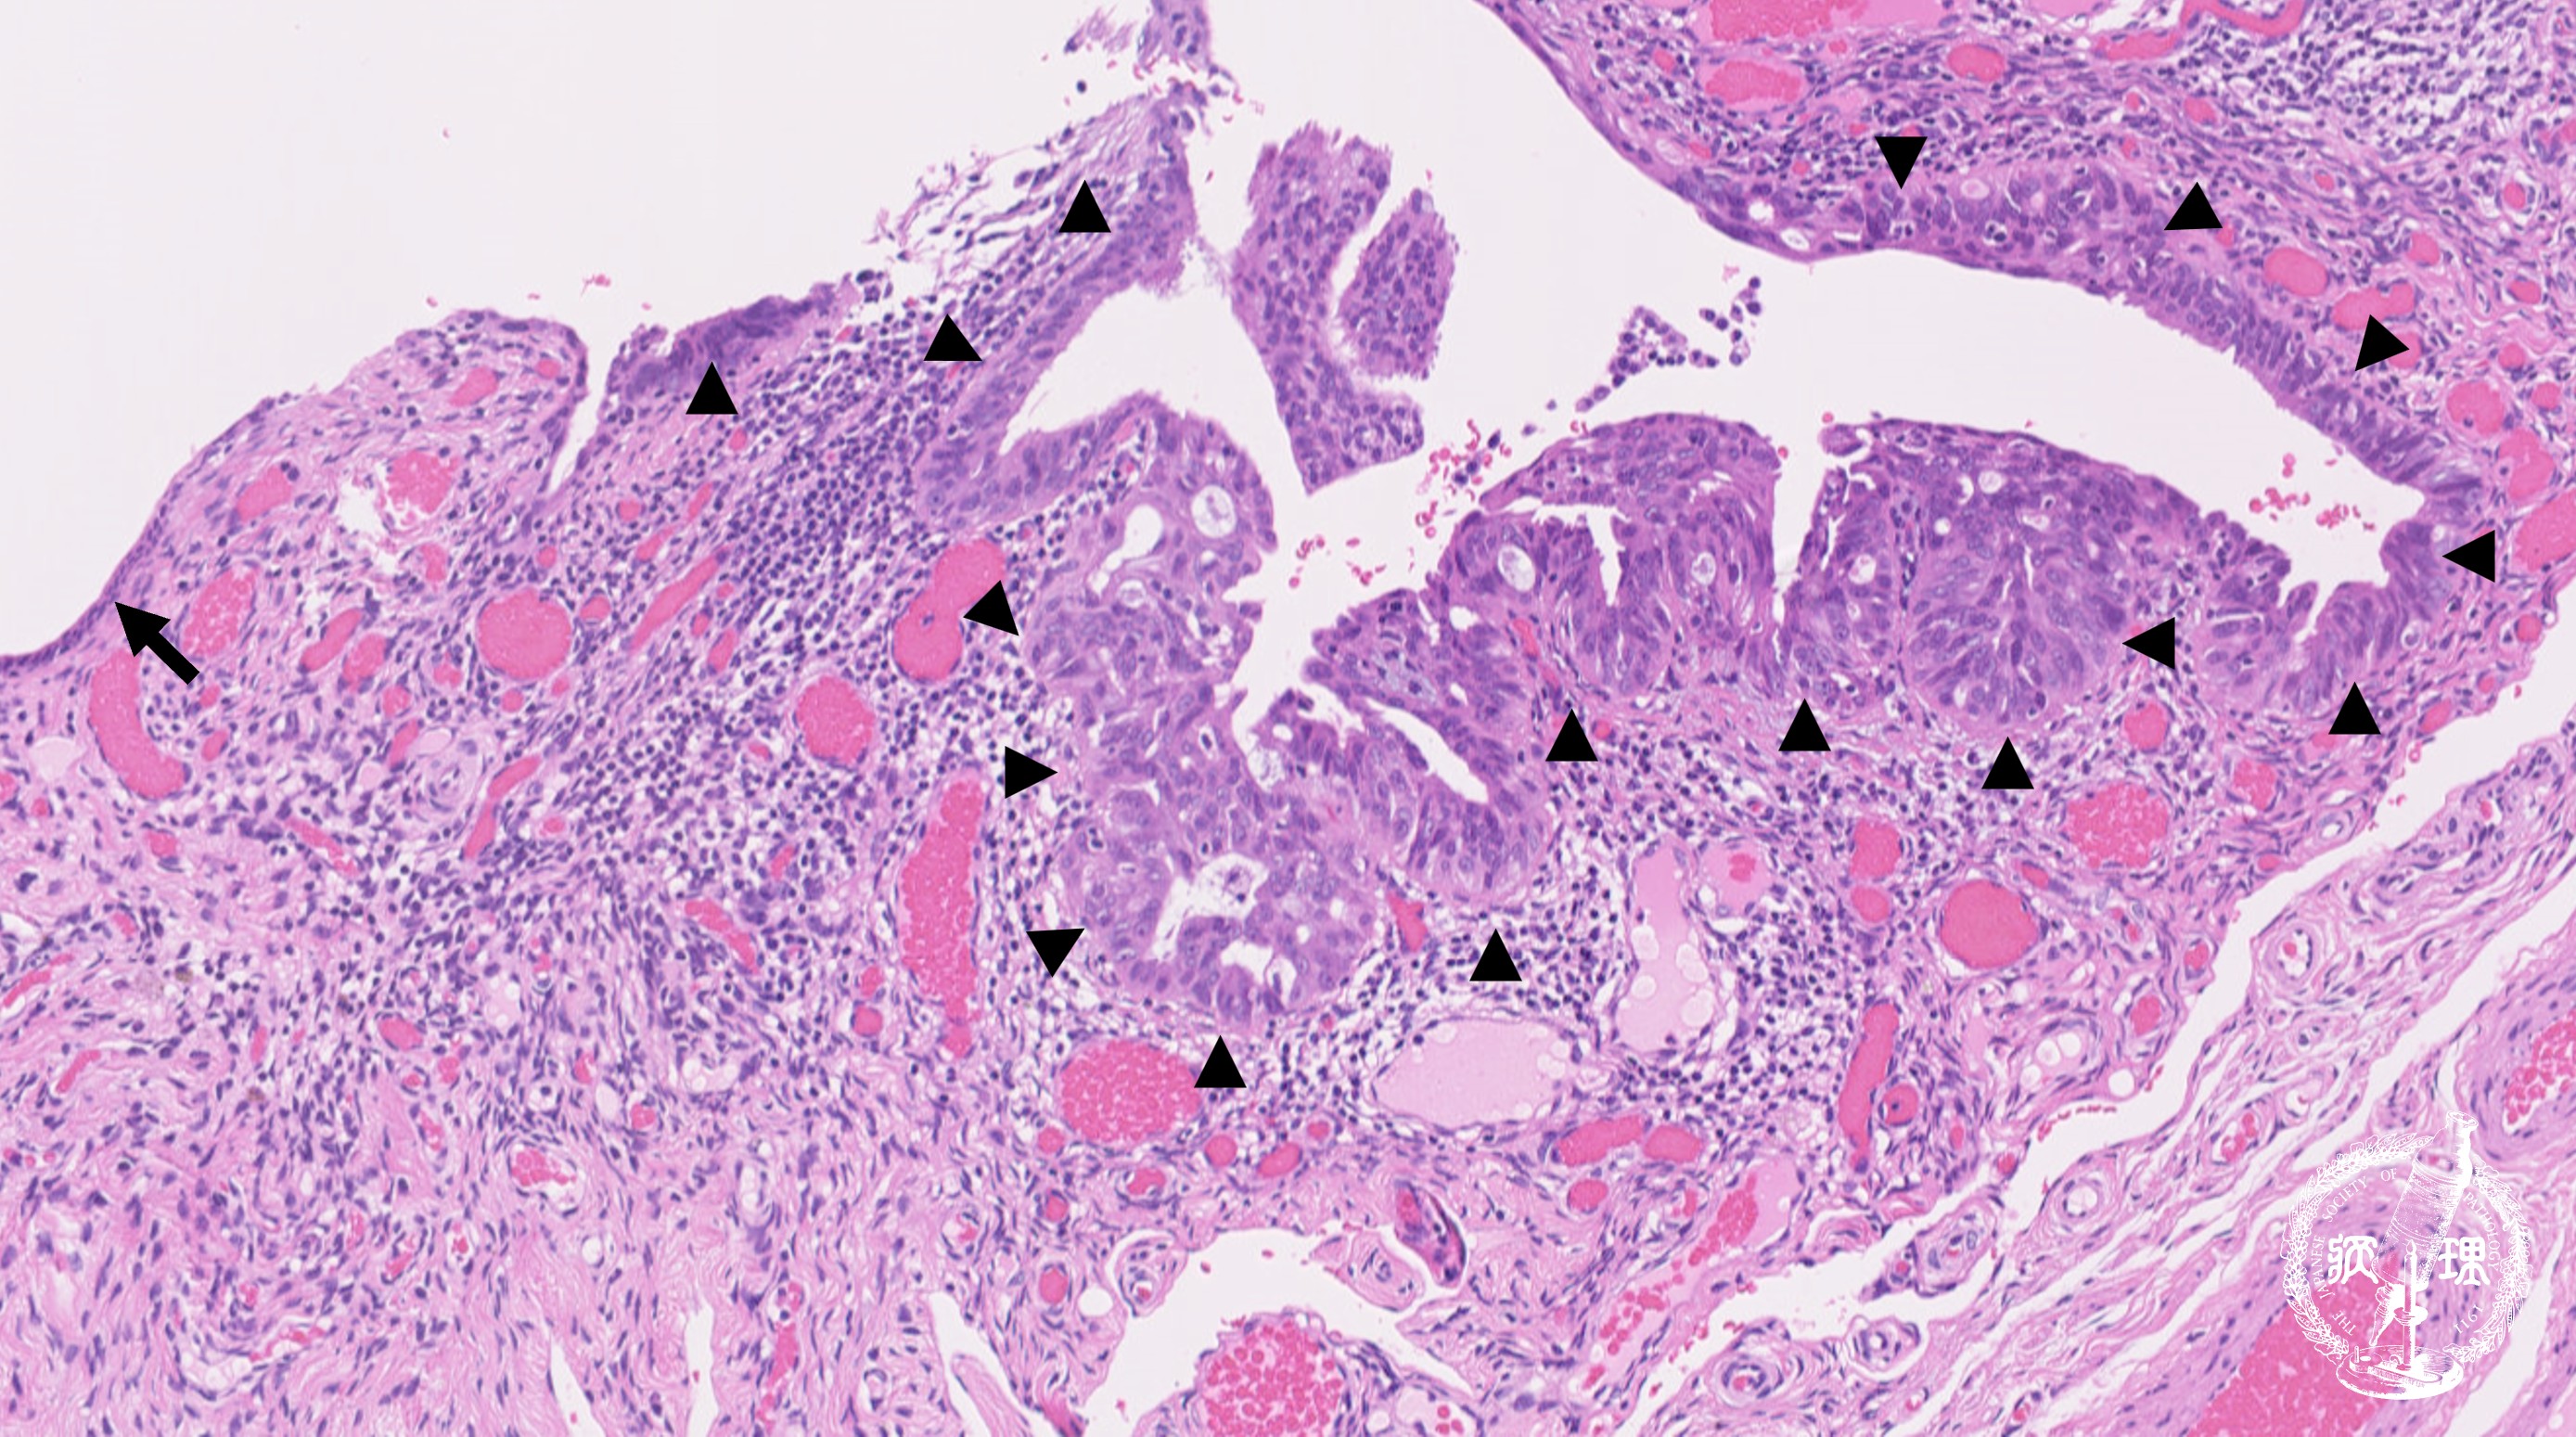

ミクロ像 (HE弱拡大):卵管采上皮。既存の卵管采上皮を置換するように、濃染腫大核を有する腫瘍細胞が密に増生している。左側には正常の卵管上皮 が残存している(矢印)。